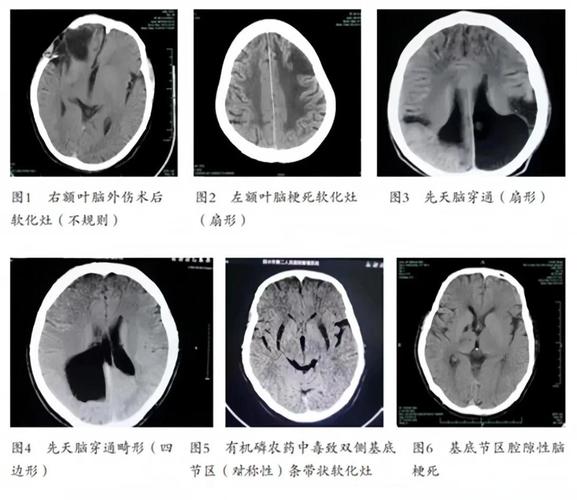

脑软化,更准确的医学术语是脑梗死灶或脑软化灶,是脑组织坏死后的一种终末状态。

脑软化灶本质上就是一个“脑组织的疤痕”,它标志着此处曾经发生过脑梗死或其他类型的脑组织损伤(如外伤、出血等)。